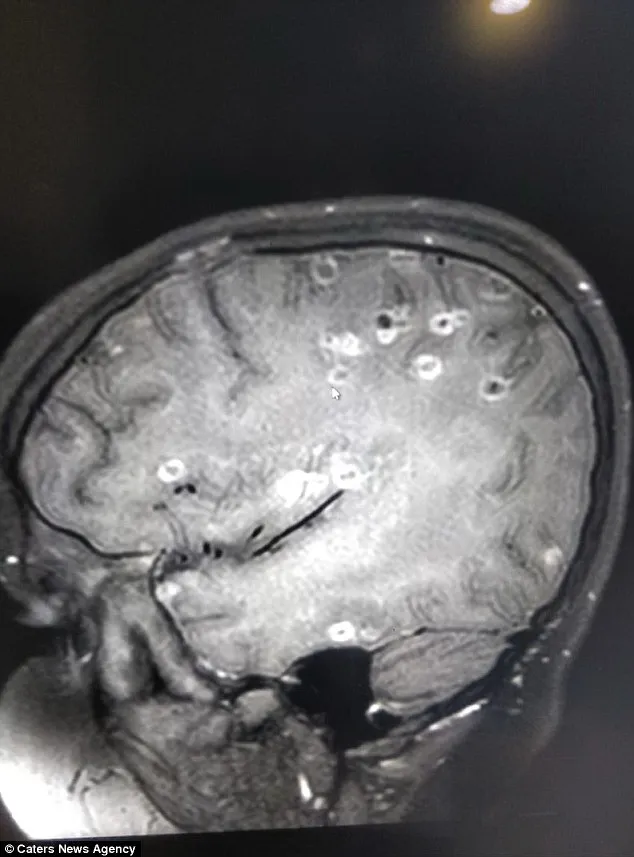

Sáu tháng sau, gia đình đưa cô bé đến BV Fortis ở Gurgaon. Tại đây, bản phim chụp cho thấy cô bé bị mắc một hội chứng gọi là loạn thần kinh neurocysticercosis. Trong não cô bé có hơn 100 chấm trắng biểu thị cho trứng sán dây.

Hình ảnh trên phim chụp cho thấy não bé gái có tới 100 chấm trắng biểu hiện cho trứng sán dây. Ảnh: Dailymail